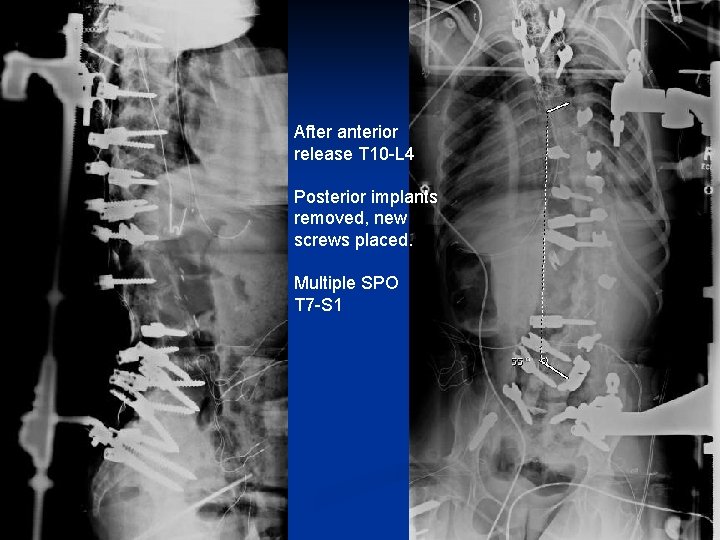

n n Case 3: Intraoperative compression for SPO in fixed deformity 15 year old female CP GMFCS 4 progressive neuromuscular scoliosis. Motor WC PSFI at age 10 years. Never was happy with post op balance. Difficulty sitting. Iliac screw eroding through skin and severe back pain.

Fixed spine deformity

Original surgery Was never Balanced Now pain and broken implants 72 degree scoliosis

After anterior release T 10 -L 4 Posterior implants removed, new screws placed. Multiple SPO T 7 -S 1

Gradual 6 cm shortening of femoral compressor Rods placed.